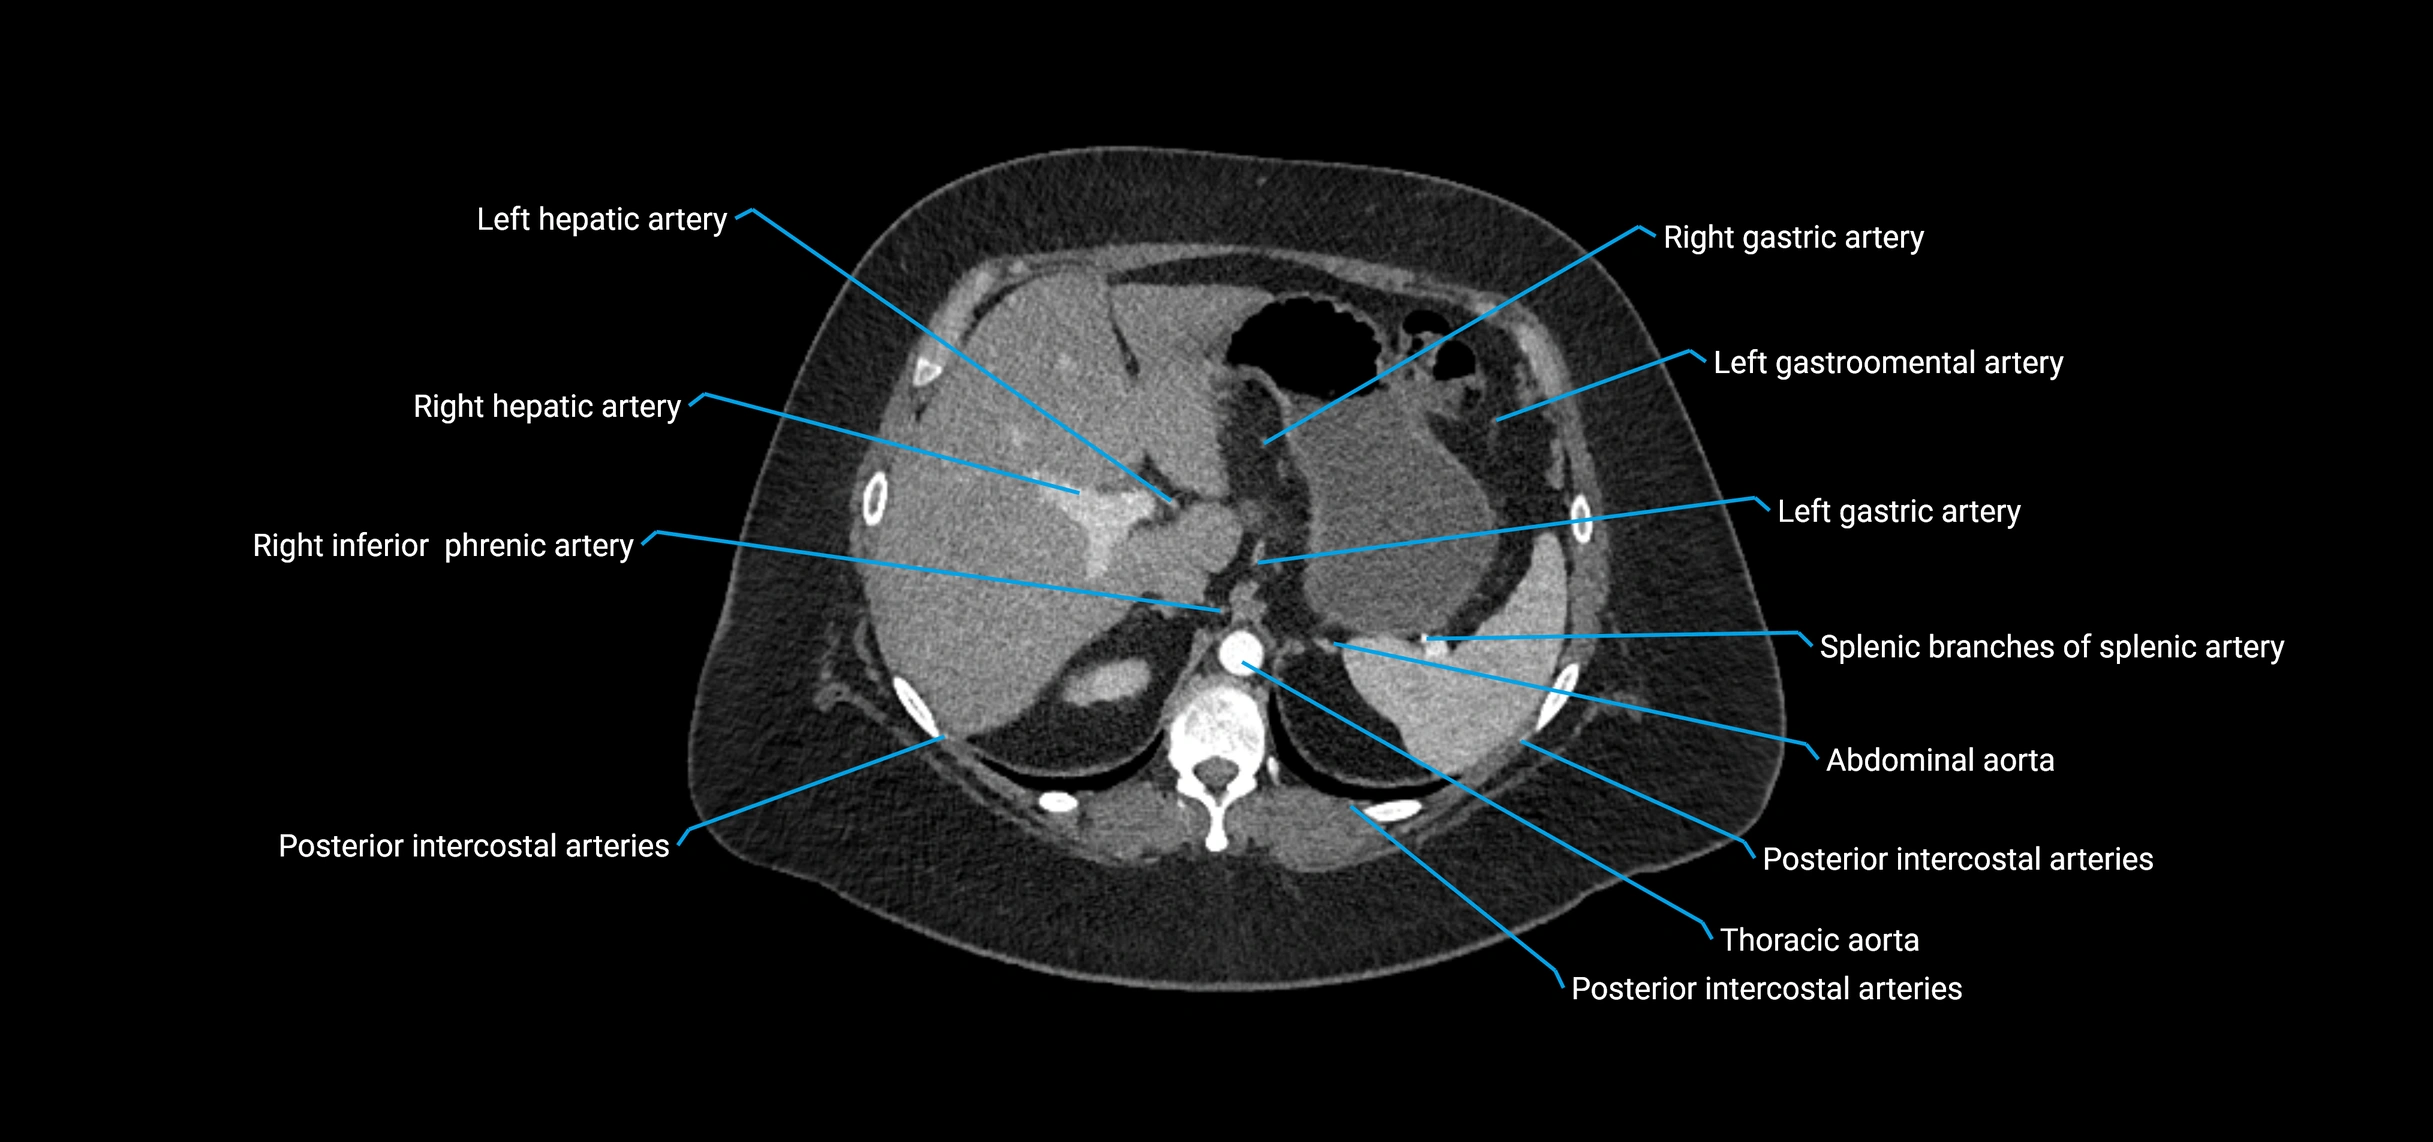

Contrast-enhanced CT (CTA):

• Gold standard for abdominal aortic imaging

• Provides excellent detail of lumen, wall, aneurysm, thrombus, and branch vessels

• Multiplanar and 3D reconstructions help in aneurysm measurement, stent graft planning, and dissection evaluation

• Detects acute rupture, traumatic injury, or occlusion with high sensitivity